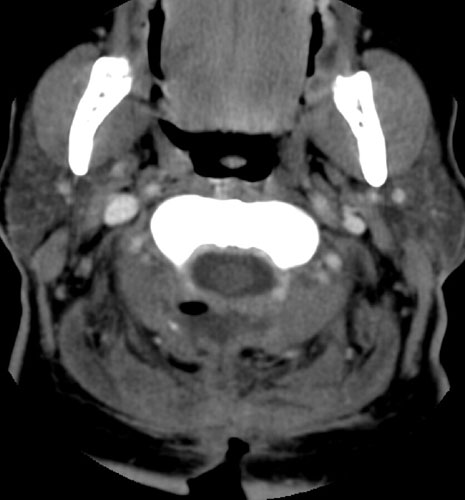

| Contrast enhanced axial CT scan demonstrates unroofing

of the spinal canal from the C2 to the C7 with bilateral laminectomies and

removal of the spinous processes. There is a fluid collection without

significant rim enhancement in the post surgical bed at the C2 level,

posterior to the spinal canal. Within this, there is some air. The fluid

collection appears to extend inferiorly to the C3 level, and then a small

slit of fluid continues inferiorly to the C5 - 6 level (not shown), where it appears

to communicate with the midline incision . |